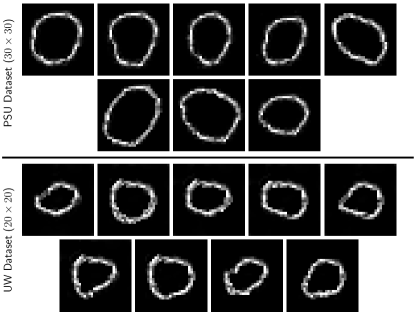

For each dataset, multiple training images are analyzed by a medical expert to hand label the nuclei boundaries. A set of representative shapes is then hand crafted by the medical expert to form the set . Some examples of the nucleus shape priors are shown in Fig. 1. These are corresponding to colon tissue images – detailed explanation is provided in Section IV. To construct a meaningful regularization term emphasizing shape priors, we need the nucleus boundary information of the input raw image . We employ the widely used Canny edge detection222Note we select Canny edge detection filter because of its simplicity and efficiency. Although its performance satisfies our intentions, other edge detection methods can also be used. filter [33] to generate the raw edge image with edges labeled as and background as , as shown in Fig. 3-(b). Note that the raw edge image is only used during the training process.

SP-CNN: layers are used as validated in Section IV-C. These layers are with ‘SAME’ padding scheme; its configuration details are provided in Table. II. We use different nuclei shapes in the domain expert provided shape set. Each shape is described by a patch for UW Dataset [5], while for the PSU dataset, we use a patch. The active part of the shapes are labeled as 1 and 0 otherwise. All the parameters used in SP-CNN are chosen by cross validation [48]. Most important of them are: trade-off values and , pooling window size , weight decay parameter = , learning rate decay = , where the trade-off parameters are selected by cross-validation and the effect of these parameters is shown in Table I.

TSP-CNN: The parameters in TSP-CNN are same as SP-CNN except for the trade-off parameters which are or and , and number of layers which is chosen (as per Section IV-C) to be . With this parameter setting, the Basis Shape Set using TSP-CNN for the UW-dataset converges to basis shapes, while for the PSU dataset shapes are determined. For both datasets, the optimized Basis Shape Set is visualized in Fig. 7.